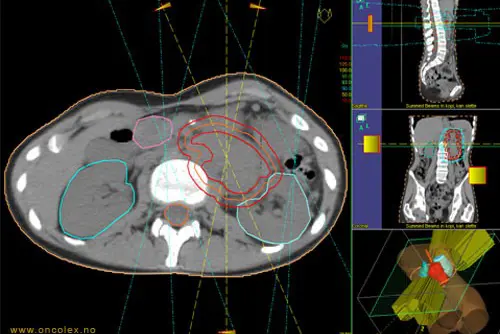

All strålebehandling er individuelt tilpasset. For at behandlingen skal kunne planlegges og gjennomføres, kreves godt tverrfaglig samarbeid av et fagteam bestående av leger, medisinske fysikere og stråleterapeuter. Legene vurderer sykdomsbildet og avgjør hvilket område som skal behandles samt hvor høy stråledose som skal gis. Antall behandlinger (fraksjoner) varierer avhengig av svulstens type, størrelse, lokalisasjon og hensikten med behandlingen. Stråleterapeuter og medisinske fysikere planlegger og kvalitetssikrer behandlingen.